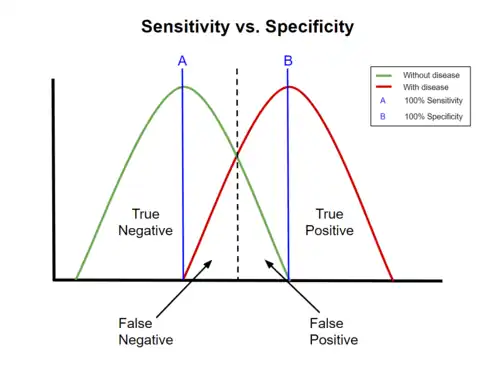

Graphical illustration

-

A graphical illustration of sensitivity and specificity

A graphical illustration of sensitivity and specificity

The above graphical illustration is meant to show the relationship between sensitivity and specificity. The black, dotted line in the center of the graph is where the sensitivity and specificity are the same. As one moves to the left of the black dotted line, the sensitivity increases, reaching its maximum value of 100% at line A, and the specificity decreases. The sensitivity at line A is 100% because at that point there are zero false negatives, meaning that all the negative test results are true negatives. When moving to the right, the opposite applies, the specificity increases until it reaches the B line and becomes 100% and the sensitivity decreases. The specificity at line B is 100% because the number of false positives is zero at that line, meaning all the positive test results are true positives.